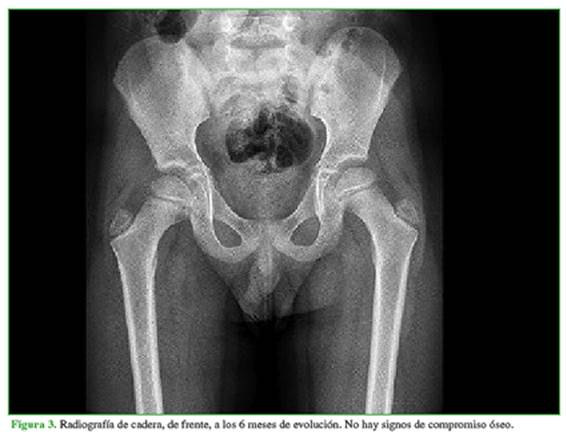

Se solicitaron estudios por imágenes que incluyeron radiografías y ecografía de ambas caderas. En los estudios radiográficos, no se observaron lesiones óseas ni de partes blandas con ambos espacios articulares conservados. La ecografía de cadera derecha mostró un derrame articular con un despegamiento de 7 mm de la cápsula articular (Figura 1). Con estos resultados y ante la sospecha de un cuadro de sinovitis transitoria, se inicia un tratamiento ambulatorio con agentes antinflamatorios por vía oral.